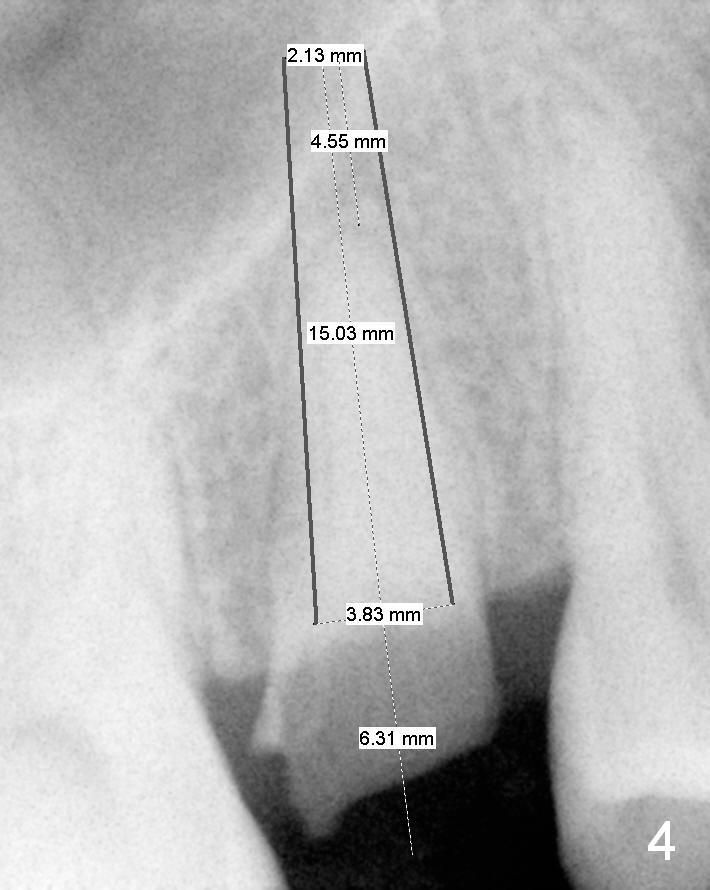

A 52-year-old woman (LP) has postponed extraction and implant for the tooth #4 for 10 years (Fig.1). The socket is oval in cross section, great site for D Implant. D2 (3.5x4.5 mm) short (16 mm, Fig.2) and long (20 mm, Fig.3) implants appear to be fit for the site (no antibiotic). However, placement of the latter involves bone expansion/tapping, which is incompatible with the fearful lady. Let us be gentle (Fig.4).